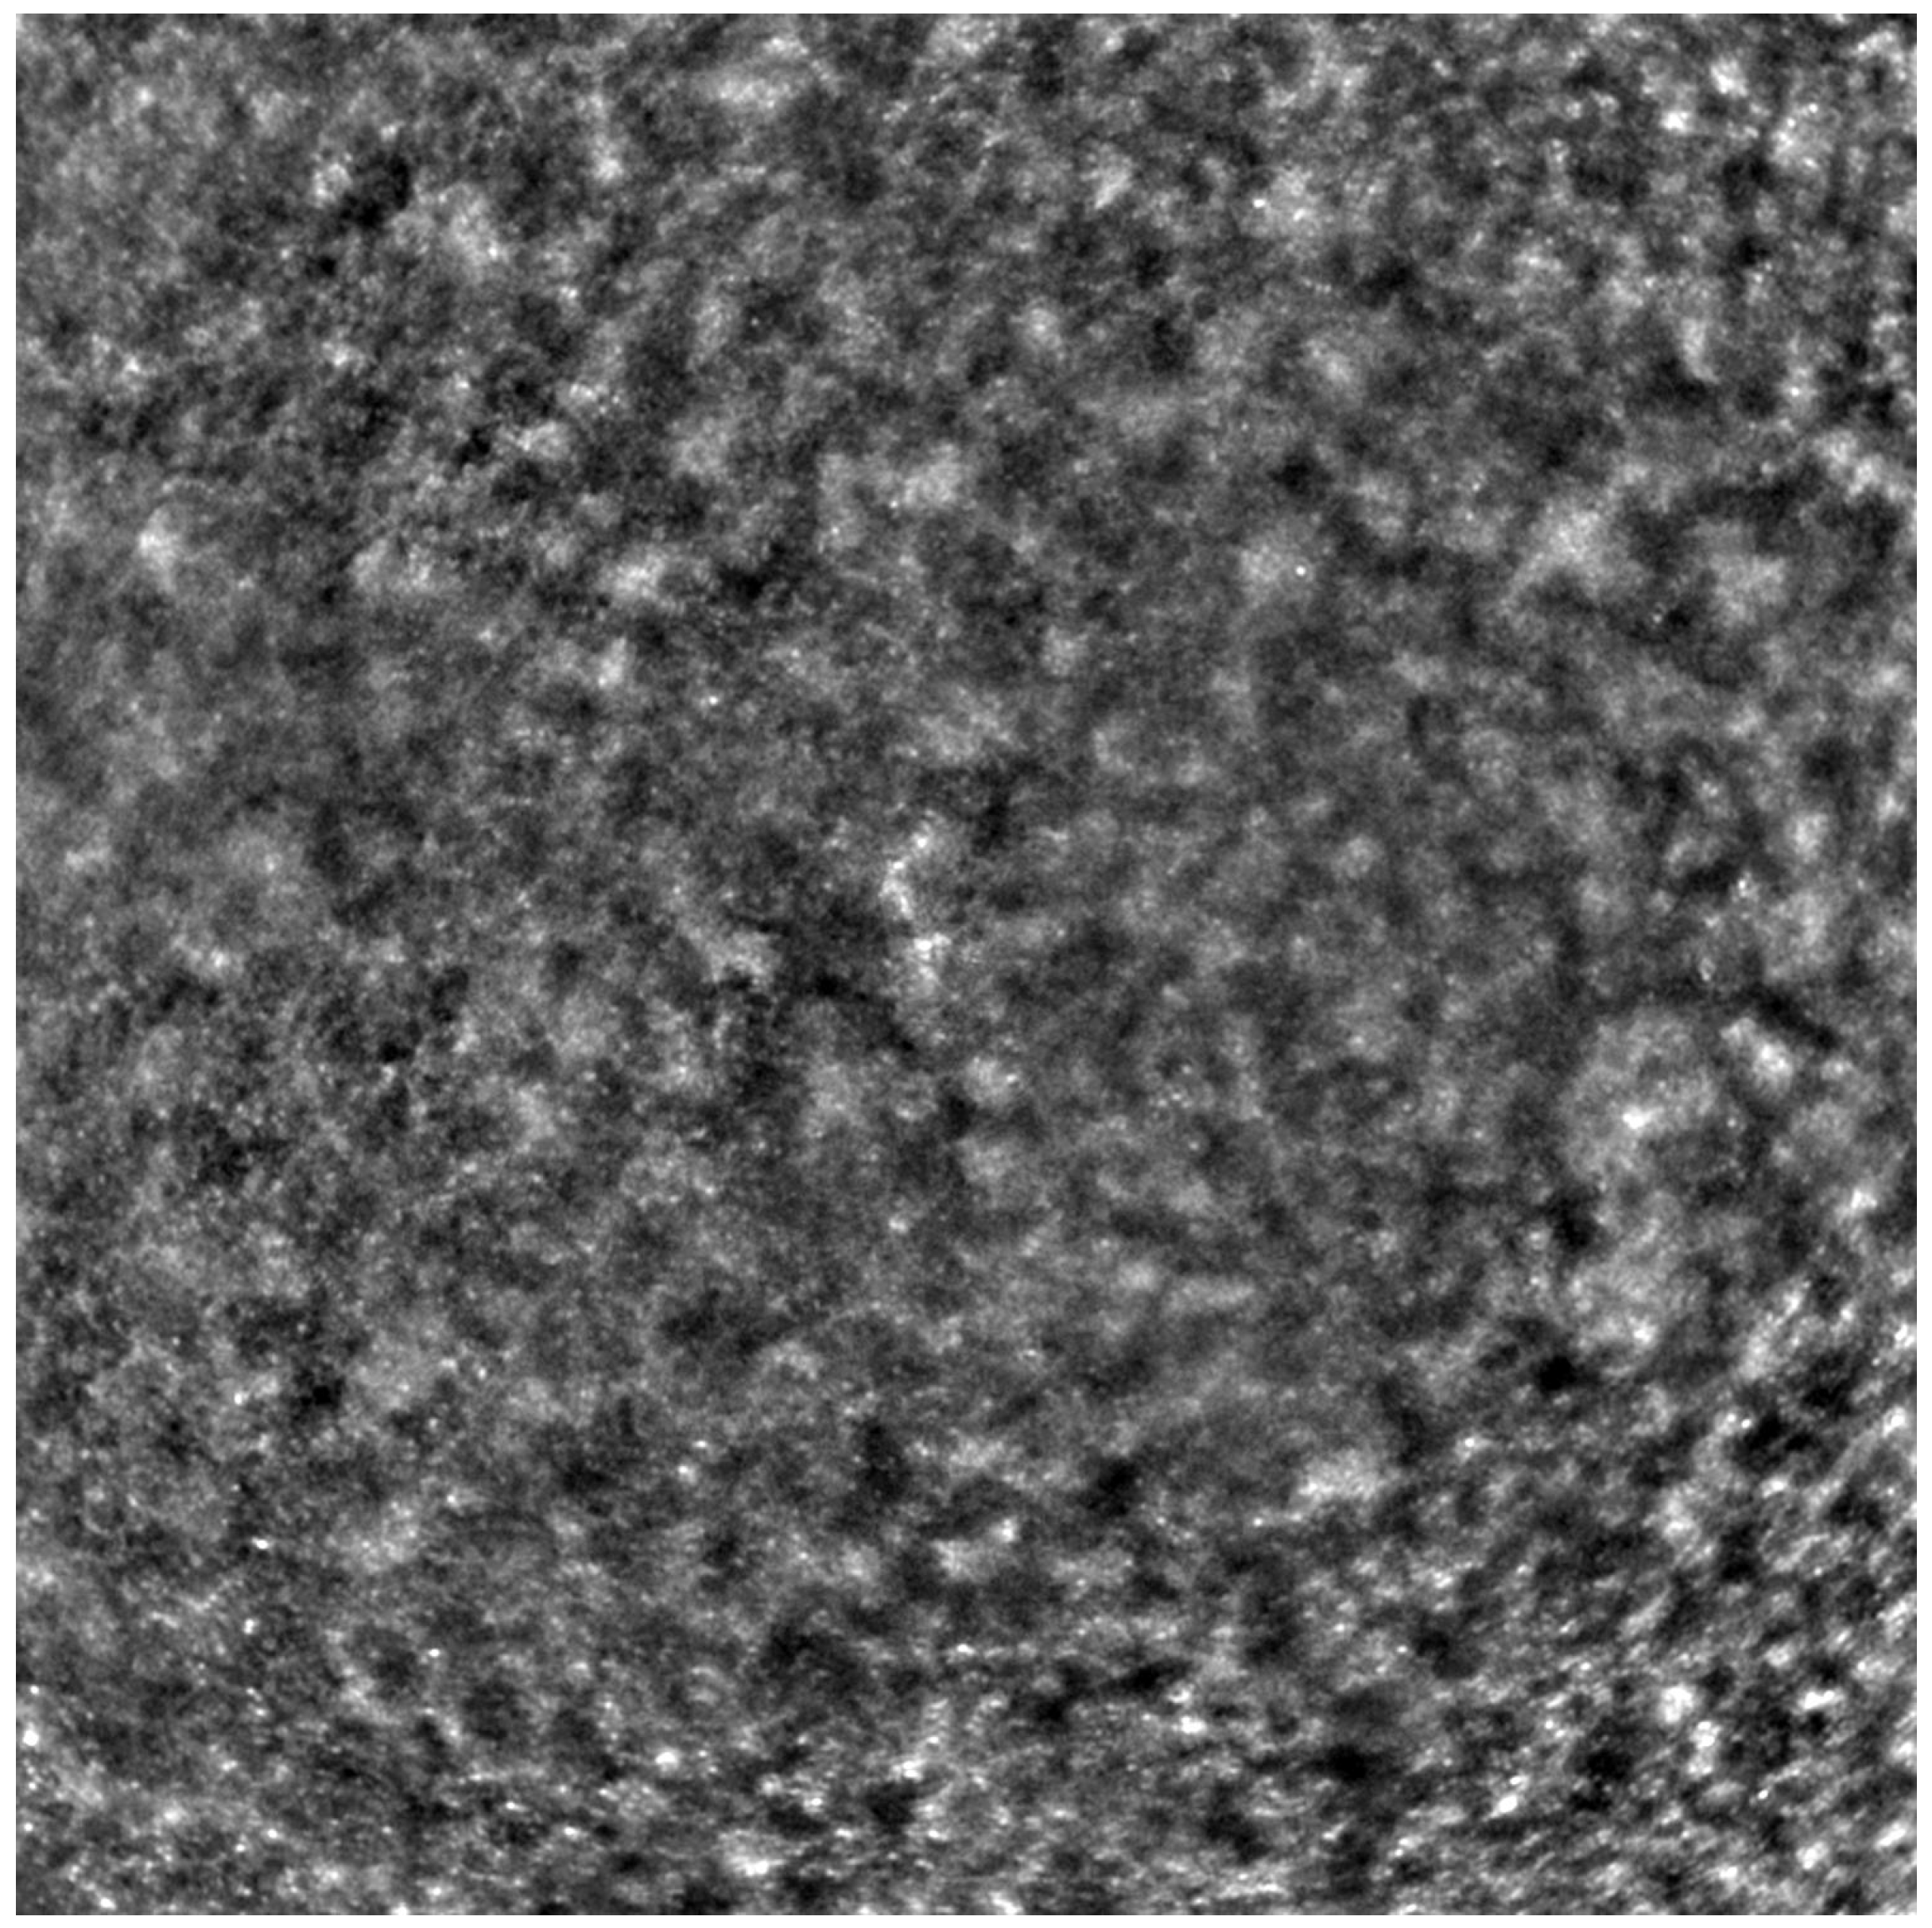

Adaptive optics retinal images depicting a healthy eye, CD, CRD, and STGD are presented in Figure 1, Figure 2, Figure 3 and Figure 4.

Cone mosaic disruption is an abnormality typical of IRDs. The cone and rod spacing is increased in IRDs compared to healthy retinas [18]. Additionally, poor image quality, likely resulting from inadequate fixation in eyes with low visual acuity, is a problem that, in some cases, makes image acquisition impossible [19,20]. In STGD, as well as in other IRDs, the “dark spaces” depicting areas of disrupted cone structure and abnormal cone reflectance have been described [21,22].

Figure 2. An adaptive optics image of the photoreceptors of an eye afflicted by cone dystrophy (Rtx1™, Imagine Eyes, France). Observe the cone disruption throughout the image with “dark spaces” apparent within the cone mosaic across different areas of the image.